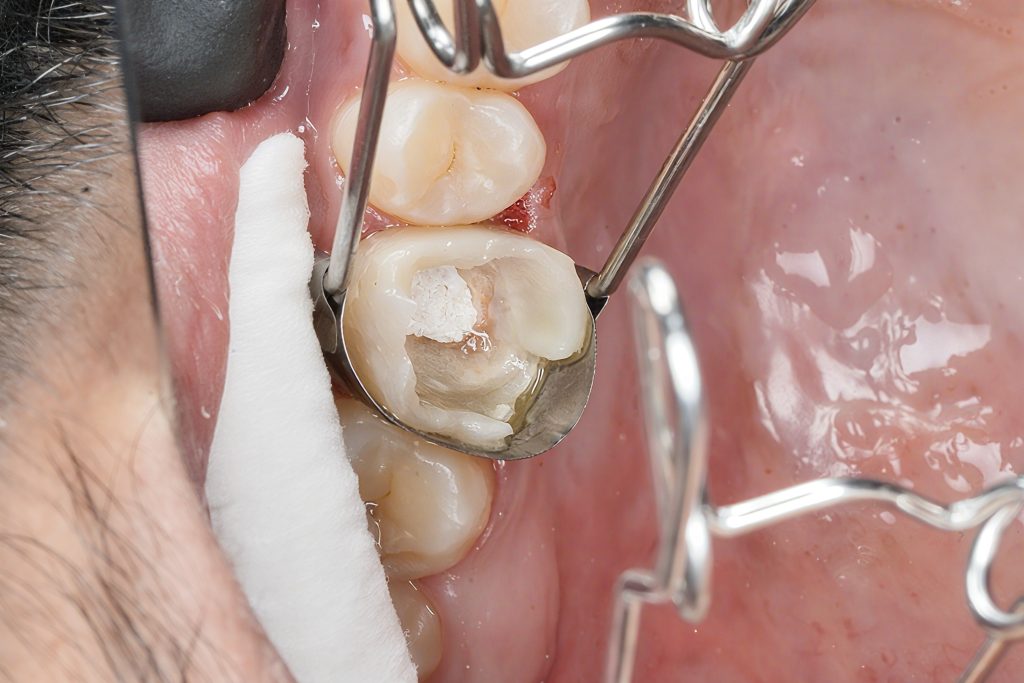

Removal of Old Restorations & Caries

After cleaning, a deep proximal margin was revealed—subgingival and not suitable for direct composite.

This indicated the need for Deep Margin Elevation (DME) to bring the margin supragingival.

Matrix & Isolation

A sectional matrix was placed under isolation to reconstruct the proximal wall predictably.

Adhesive Protocol

Selective Enamel Etch

Self-etch universal adhesive (Kuraray Clearfil, Tokuyama Universal Bond, or 3M Scotchbond Universal Plus)

- Enamel etched separately for stronger micromechanical retention

- Dentin left moist and treated with self-etch to avoid collagen collapse

DME Build-Up

A flowable base was placed first for adaptation, followed by a packable composite.

The goal was to:

- Seal the cervical margin

- Create a supragingival, easily cleanable finish line

- Provide a stable platform for the onlay